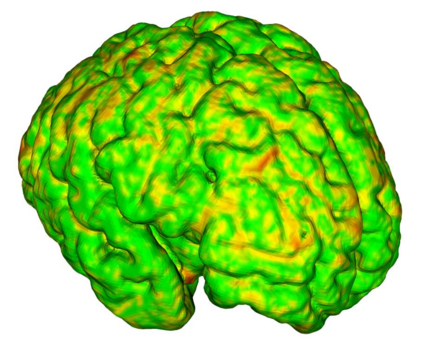

Fetal cortical plate segmentation is essential in quantitative analysis of fetal brain maturation and cortical folding. Manual segmentation of the cortical plate, or manual refinement of automatic segmentations is tedious and time-consuming. Automatic segmentation of the cortical plate, on the other hand, is challenged by the relatively low resolution of the reconstructed fetal brain MRI scans compared to the thin structure of the cortical plate, partial voluming, and the wide range of variations in the morphology of the cortical plate as the brain matures during gestation. To reduce the burden of manual refinement of segmentations, we have developed a new and powerful deep learning segmentation method. Our method exploits new deep attentive modules with mixed kernel convolutions within a fully convolutional neural network architecture that utilizes deep supervision and residual connections. We evaluated our method quantitatively based on several performance measures and expert evaluations. Results show that our method outperforms several state-of-the-art deep models for segmentation, as well as a state-of-the-art multi-atlas segmentation technique. We achieved average Dice similarity coefficient of 0.87, average Hausdorff distance of 0.96 mm, and average symmetric surface difference of 0.28 mm on reconstructed fetal brain MRI scans of fetuses scanned in the gestational age range of 16 to 39 weeks. With a computation time of less than 1 minute per fetal brain, our method can facilitate and accelerate large-scale studies on normal and altered fetal brain cortical maturation and folding.